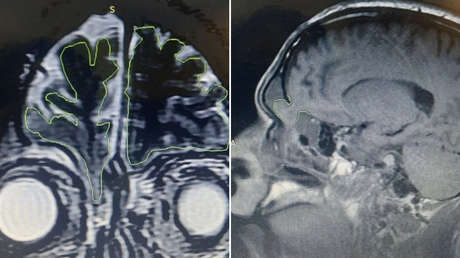

El hombre fue sometido a investigaciones radiológicas, que mostraron que tenía una fractura de base con un encefalocele, que es una afección en la que la materia del cerebro empieza a salir por orificios del cráneo, como la cavidad nasal.

Generalmente, el encefalocele es un defecto congénito poco frecuente. En este caso, la afección se generó luego de que el hombre rechazara el tratamiento inicial de las lesiones cuando acudió al hospital tras sobrevivir al accidente de tráfico, por lo que desarrolló una meningoencefalitis dos meses antes de acudir al hospital por la fuga nasal.